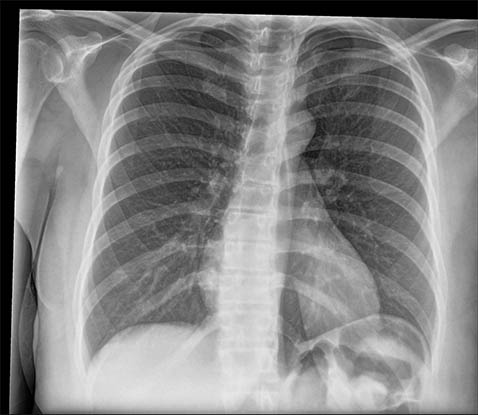

SmartGrid 处理的影像质量与使用防散射滤线栅采集的影像相当,但床边胸部影像方面患者剂量会减少。它会抑制散射的作用,从而改善解剖结构对比度。在不使用防散射滤线栅的情况下,滤线栅状影像质量的好处是加快工作流程并方便放射科技师成像。